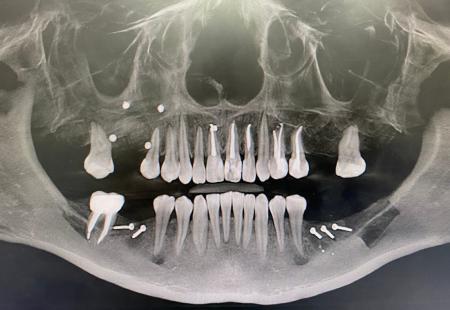

Тотальная реабилитация Пациента Л.

- Ревизия очагов хронической инфекции в полости рта.

- Ортодонтическое лечение (Кадиева И.Ф)

- Установка ортодонтических минивинтов , на этапах лечения и восстановления прикуса пациента.

- Дентальная имплантация на нижней челюсти в области жевательной группы зубов.

- Дентальная имплантация на верхней челюсти в области жевательной группы зубов.

- Костная пластика (открытый синуслифтинг справа) в области верхней челюсти справа.

- Пластика мягких тканей в области имплантатов верхней и нижней челюсти.

- Временное протезирование (Жданов И.И) на верхней и нижней челюсти.

- Постоянное протезирование верхней и нижней челюсти. (Жданов И.И)